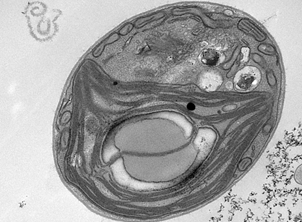

| 图2.金黄色葡萄球菌在低于药物MIC作用后细胞壁发生溶解 | |